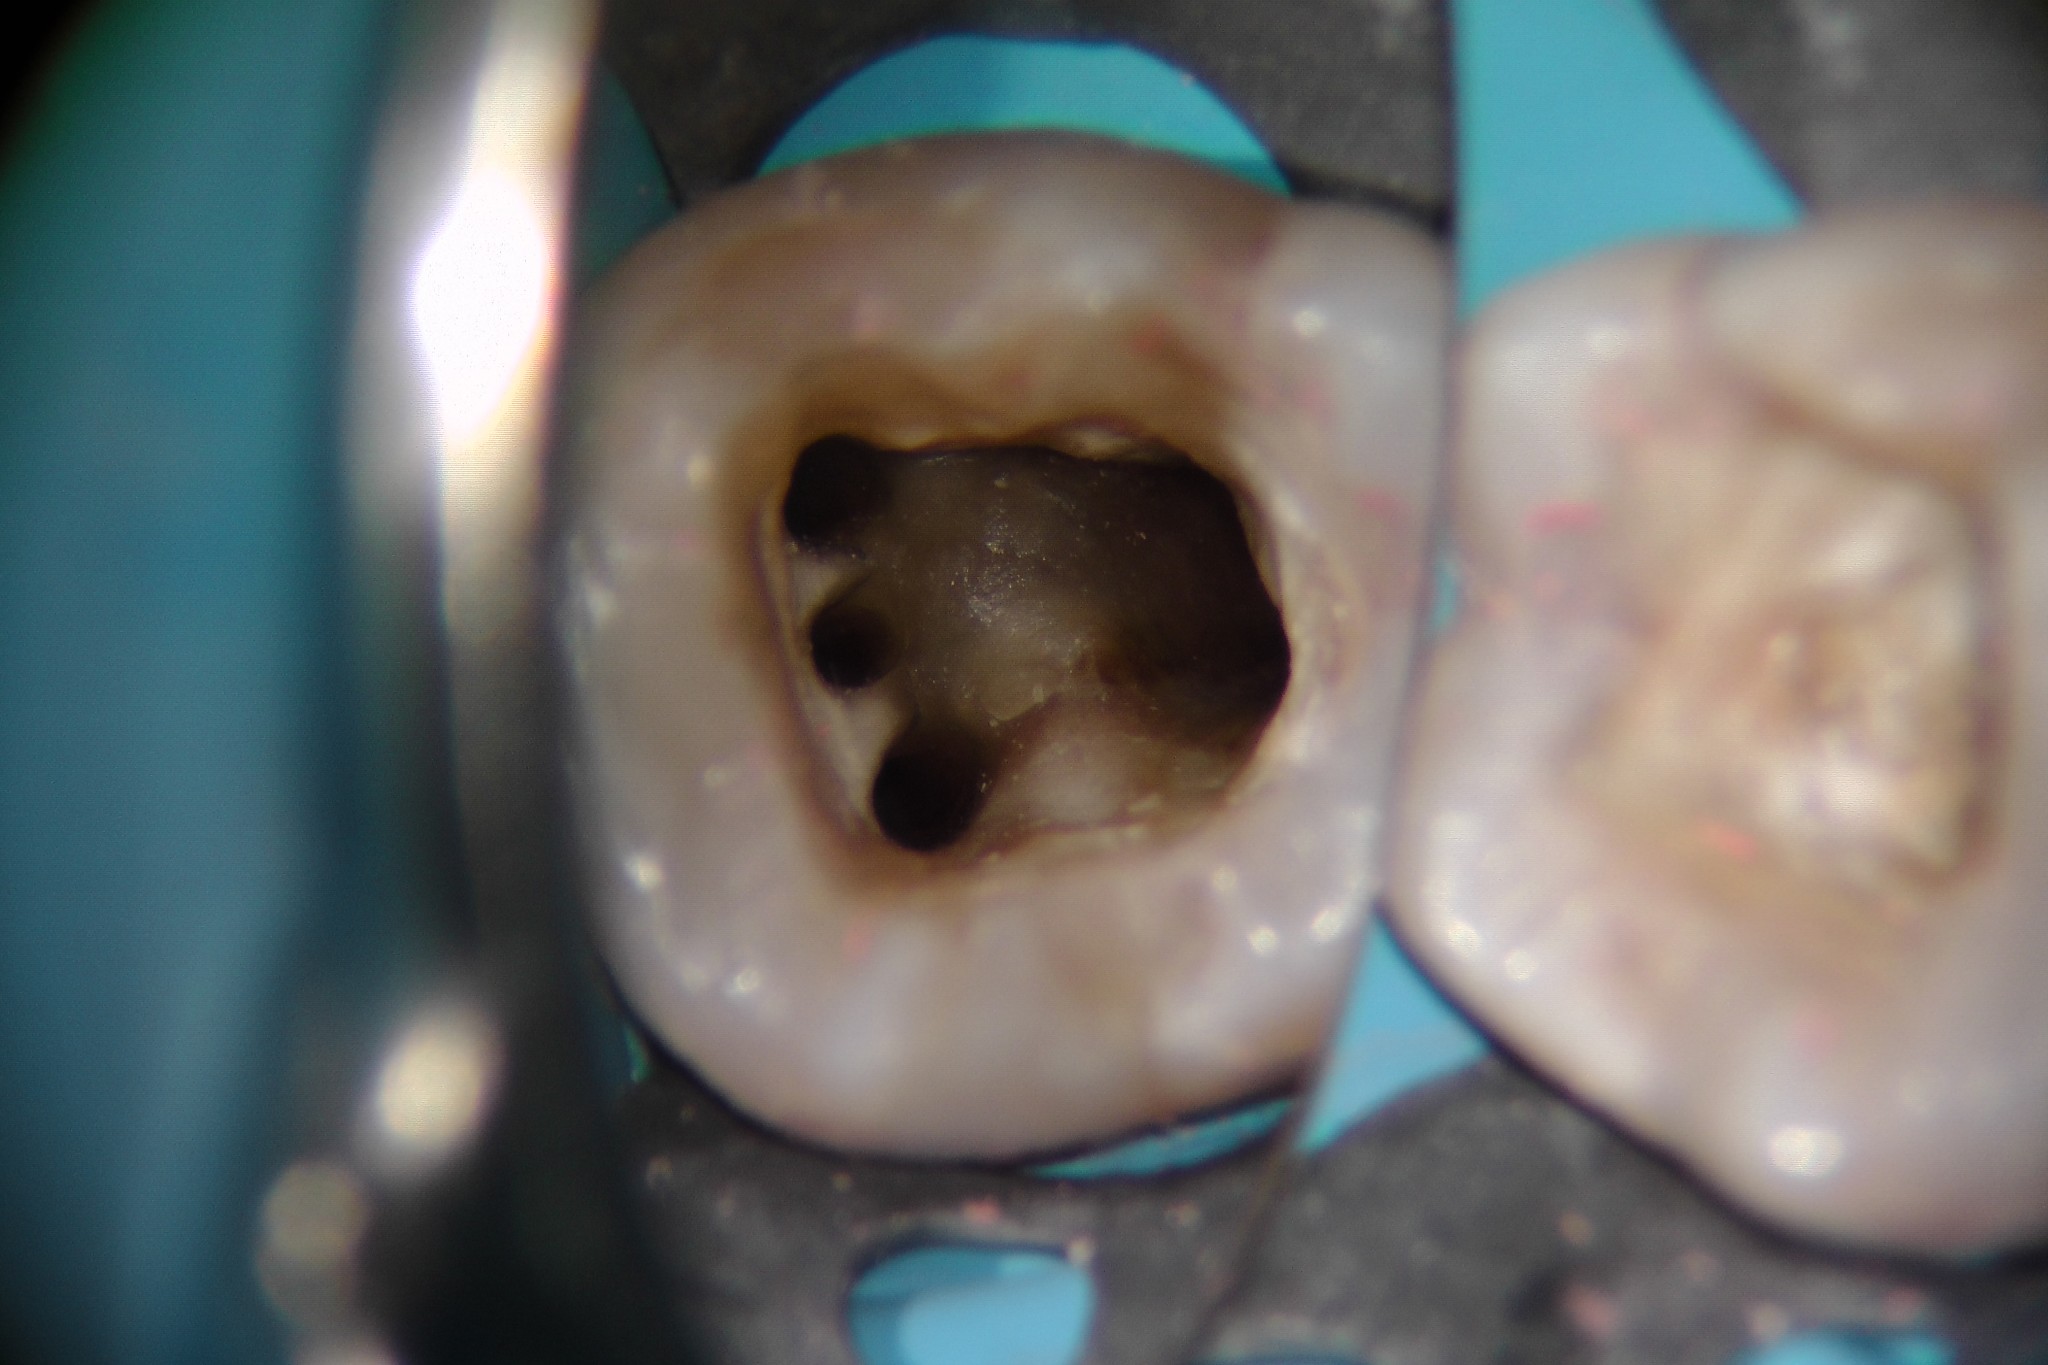

Canale Mesio-centrale - Foto 4.7

Da allora su 48 primi molari ho trovato il canale mesiale-mediano 24 volte in 17 mesi! Percentuale di 50%!!!

Di solito, essendo l’Mtwo viola uno strumento fenomenale per reperire e sondare in un sol colpo i canali stretti o calcificati, dopo aver sagomato i canali MV e ML provo a inserire questo strumento più volte nell’istmo tra i due canali suddetti. Se non sento un impegno allora mi approfondisco di 2 mm tra i canali MV e ML con una StartX 3 o , più spesso, con una fresina diamantata larga 0,8 in punta e il gioco è fatto.

Ora ti mostro qua sotto come reperire il canale mesiale-mediano.